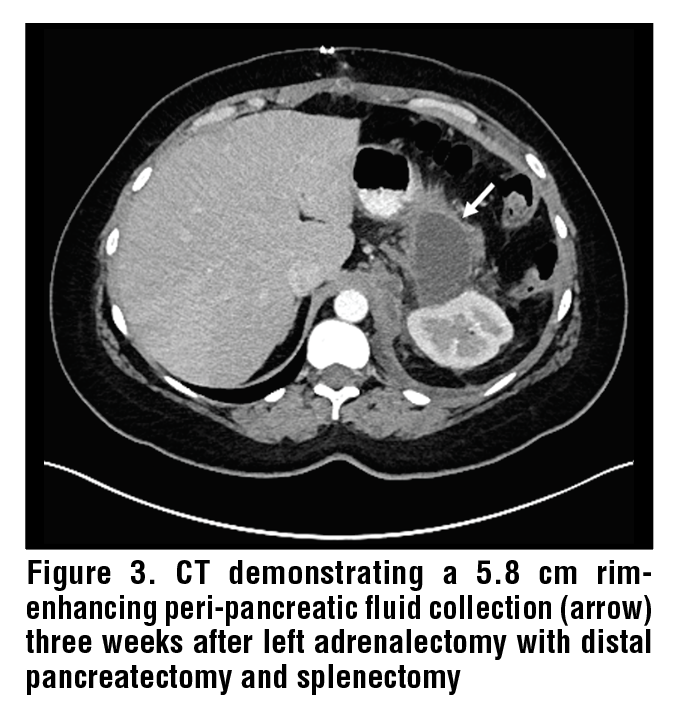

PD leaks can also occur post-operatively after pancreatic resection or inadvertent pancreatic injury during surgery of nearby organs such as the spleen, left kidney, colon, and left adrenal gland. (See Figure 3.) In the setting of pancreatic resection, PD leaks can complicate up to 5-29% of cases depending on the health of the underlying pancreatic tissue, extent of pancreatic resection, and main PD diameter.10–13